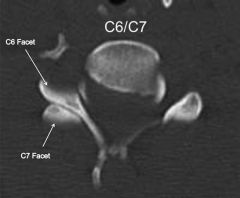

On the axial CT: Look for the Reverse Hamburger Bun Sign of the facet joints: (Case courtesy of Dr Noyan Zenger, Radiopaedia.org)

Normal Hamburger Sign: